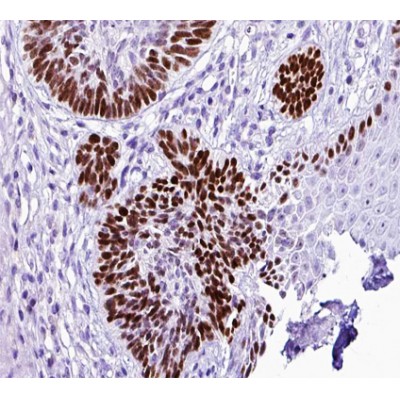

ab10384 at 1/100 staining human skin cancer tissue sections by IHC-P. The tissue was formaldehyde fixed and a heat mediated antigen retrieval step in citrate buffer was performed. The tissue was then blocked and incubated with the antibody for 1.5 hours at 22°C. An HRP conjugated goat anti-rabbit antibody was used as the secondary antibody....